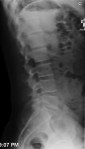

Ok, so I get hurt…..a lot. A few years ago the nurse at the local urgent care came in after taking an x-ray of my most recent boo-boo and asked me “Are you one of those X-Games people?” I could only respond, “No Ma’am, I guess I’m just one of those X-ray Games people”.

The benefit of getting hurt a lot is getting to take home a brand new x-ray to add to my collection. Yes, I collect x-rays. Aside from a nifty souvenir, its fascinating to look at what actually exists underneath all that skin. So in the spirit of being totally transparent with you people, here is what I look like with no skin on.

Of course all these x-rays come with stories, some more interesting than others, but none interesting enough to share, well except maybe the one where I sliced my finger off, or the pacemaker thing, or the…..

How about you? Got any good X-Rays? Scars? And what are stories behind them? C’mon, it’s your turn to be transparent with me.

UPDATE: A new one for the collection: